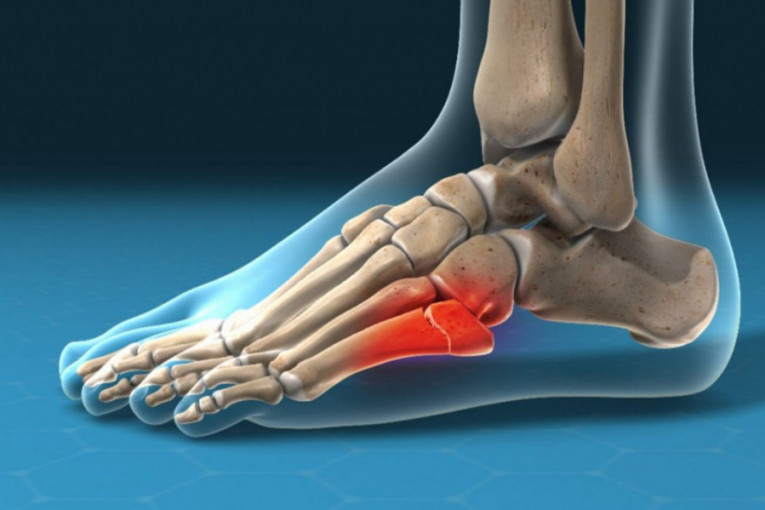

Međutim, ono što svakako brine kako sve u klubu, tako i pristalice čačanskog sportskog kolektiva, jeste detalj it 67. minutu meča kada je nakon jednog starta napadač Borca 1926 Vladimir Stevlić ostao na travi i morao je biti zamenjen.

Kasnije se ispostavilo da je došlo do preloma metatarzalne kosti, što će dvadesetsedmogodišnjeg napadača odvojiti od terena na duži vremenski period.